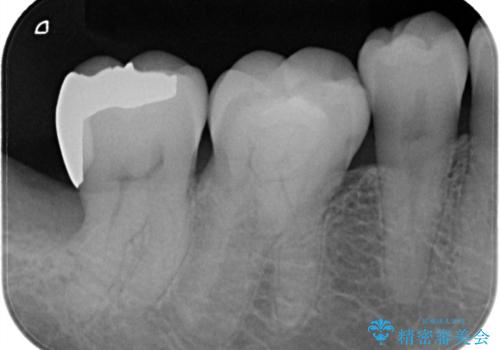

親知らずが原因の深いむし歯

- 検診にて親知らずが原因と思われる深いむし歯を発見し、親知らずを抜歯した後ゴールドインレーにて修復治療を行っております。

ゴールドインレーにて修復を行うことで適合の良い治療を行うことができました。